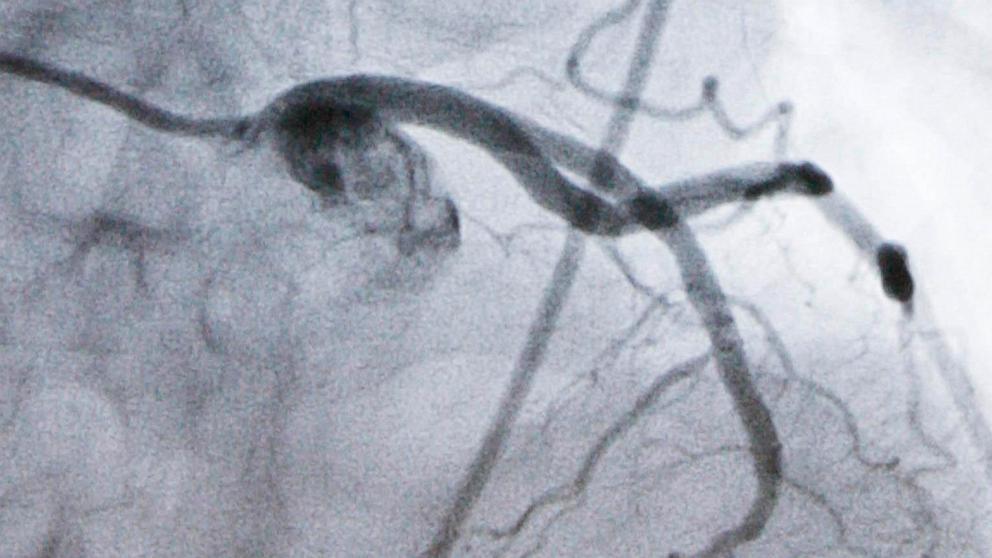

A new kind of pill sharply reduced cholesterol in people at high risk of heart attacks despite taking statins